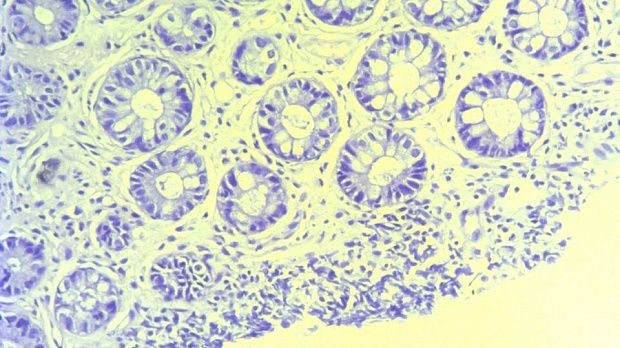

- Атлас

2 мл ( это мин сум, а мы делаем до 10 мл 3% перекись+200 мл физ раствора